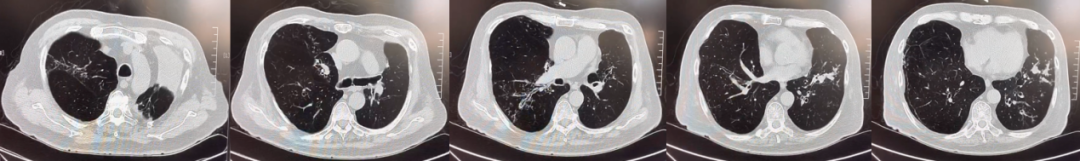

abp在医学是什么意思美例新声病例分享 | 复发活动性变应性支气管肺曲霉病(ABPA)咳嗽患者诊治经验分享_https://www.jmylbn.com_新闻资讯_第11张

入院后胸部CT-2021年10月